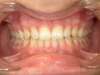

Après